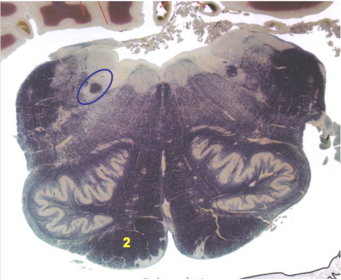

| Longitudinal pontine fibers (corticospinal tract) | |

| Transverse pontine fibers (dark fibers) | |

| Pontine nuclei (pale) | |

| Medial lemniscus | |

| ALS | |

| Trapezoid body | |

| Ventral trigeminothalamic tract | |

| Superior olive | |

| Central tegmental tract | |

| Facial nerve root fibers - descending | |

| Facial motor nucleus | |

| Interposed nuclei | |

| Medial longitudinal fasciculus | |

| Facial nerve root - internal genu | |

| Abducens nucleus | |

| Lateral vestibular nucleus | |

| Superior vestibular nucleus | |

| Inferior cerebellar peduncle | |

| Superior cerebellar peduncle | |

| Dentate nucleus | |

| Fastigial nucleus | |

| Anterior spinocerebellar tract | |

| Spinal nucleus of V | |

| Spinal tract of V | |

| Middle cerebellar peduncle | |